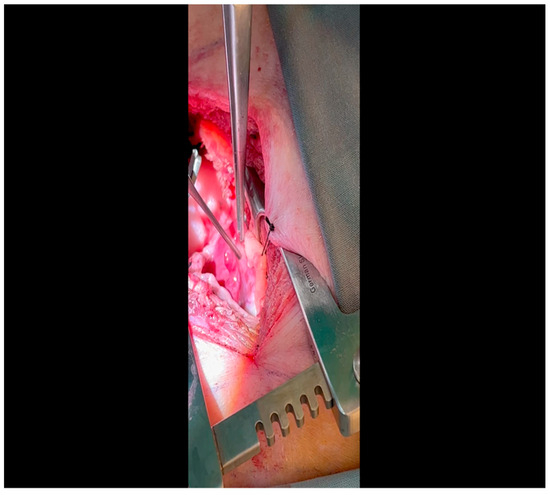

- A mini left thoracotomy is then performed: a transverse incision is made along the ribs beginning at the left sternal border and extending laterally for approximately 6 cm. This incision is placed just inferiorly to the left axillary fold (Figure 1).

- Electrocautery is used to cut through the skin and muscle of the chest wall. A Weitlaner retractor is used to retract the muscle. The intercostal muscles are divided just above the 3rd or 4th rib (Figure 2), and a Kelly clamp facilitates entry into the parietal pleura and protects the underlying intrathoracic structures as the incision is enlarged; finally, a rib spreader is placed to open the incision.